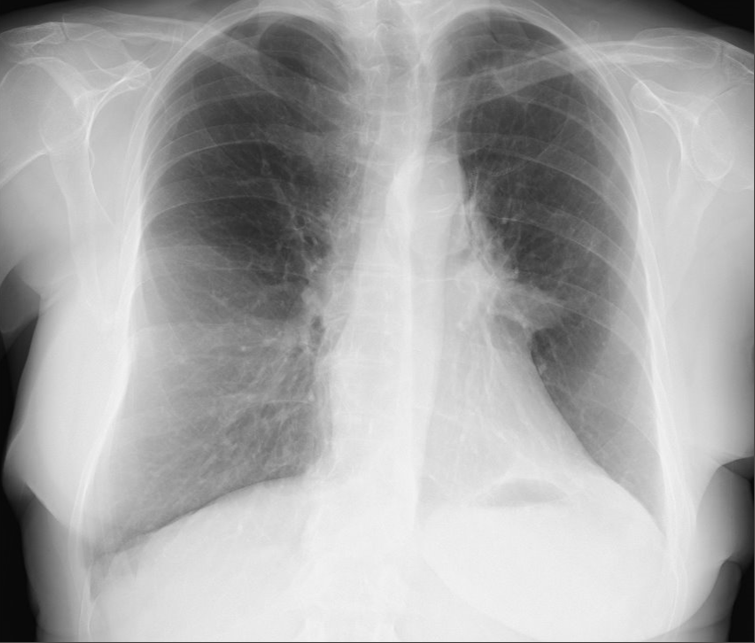

There was no postoperative air leak, and the chest tube was removed during the first postoperative day. The patient was discharged on the second postoperative day with normal chest x-ray (Figure 3). Final pathologic exam reported a 2.1 cm lepidic adenocarcinoma with free margins, and all the lymph nodes were negative for malignancy, so the final pathologic stage was pT1cN0-IA3.